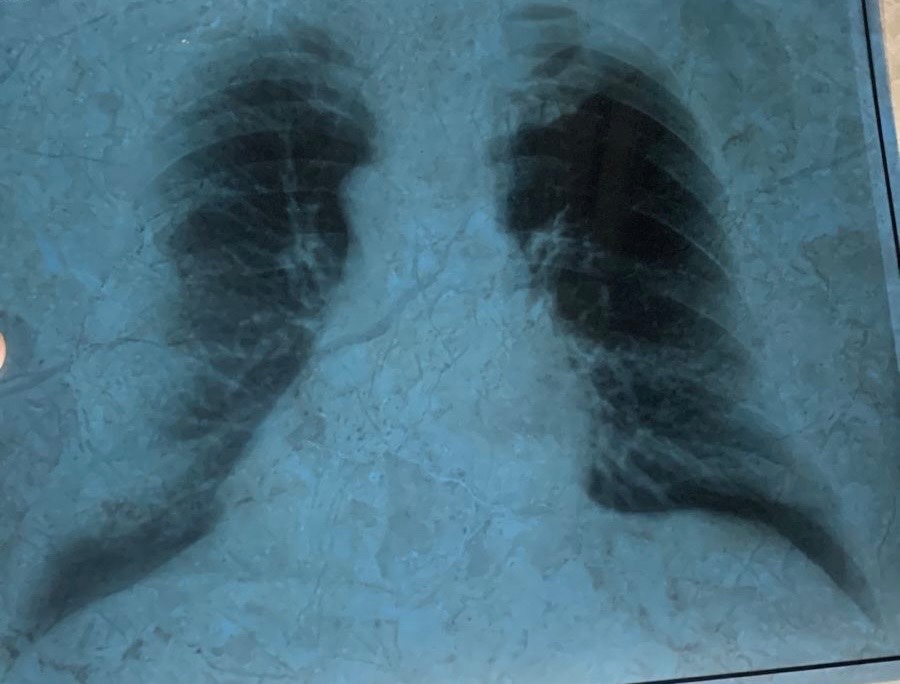

Здравствуйте. Прошу вас провести консультацию по рентгеновскому снимку органов грудной клетки моего отца. Ему 56 лет, в течение последних двух недель его беспокоит продолжительный кашель с отделением мокроты. Пожалуйста, оцените, имеются ли на снимке патологические изменения.